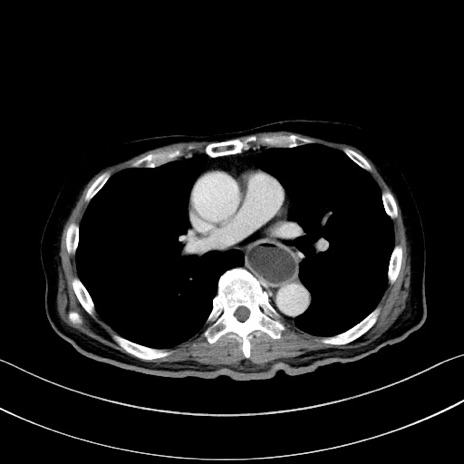

症例28(横断像)

【症例】60歳代男性

【主訴】嘔吐

【現病歴】胃癌にて胃全摘後。食思不振が悪化し、夜中に嘔吐することがある。

【既往歴】胃癌、胃全摘、脾摘、胆摘後

【データ】WBC 5900、CRP 10.56